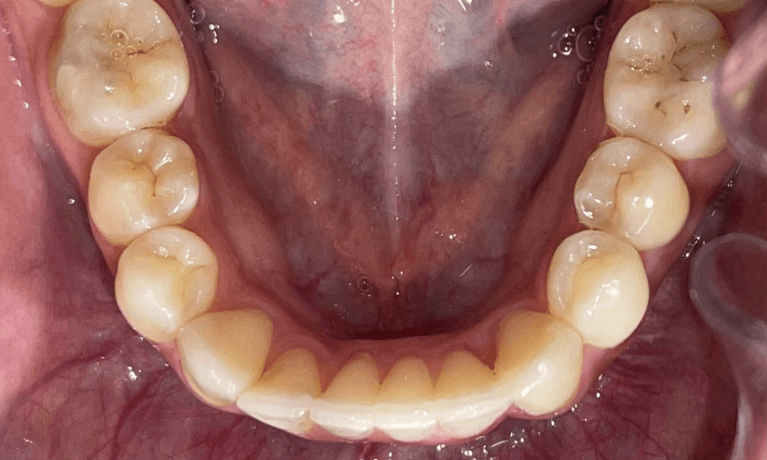

Invisalign Orthodontic treatment completed in 8 months to straighten teeth and improve esthetics.